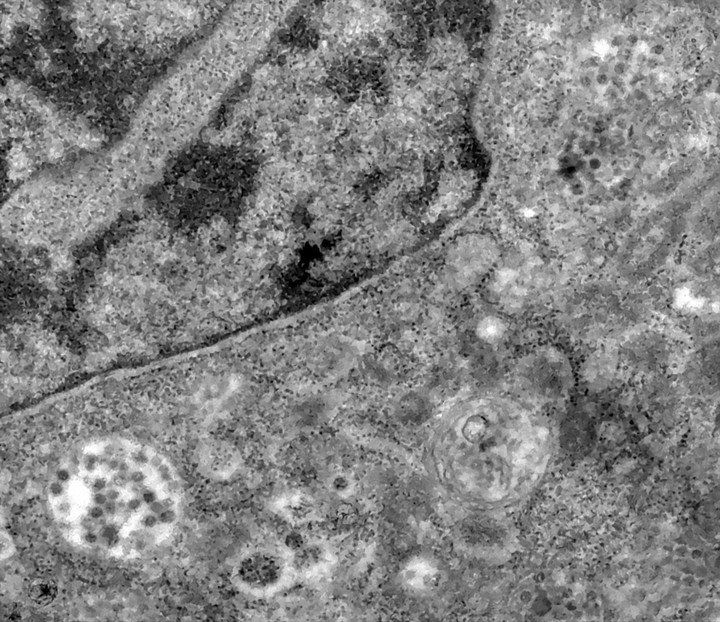

Las fotografías se tomaron con un microscopio electrónico de transmisión durante un estudio sobre replicación viral del SARS-CoV-2 y muestran con detalle el proceso de contaminación de una célula, según anunció la entidad en un comunicado.

En una de las instantáneas se observa una serie de puntos oscuros, que en realidad son partículas virales del patógeno, intentando infectar el citoplasma de la célula, en cuyo interior se encuentra el núcleo, responsable de guardar el material genético.

En una segunda imagen, el coronavirus inicia el proceso de infección y finalmente, en otra toma, ya se visualizan las partículas virales en el interior de la célula.